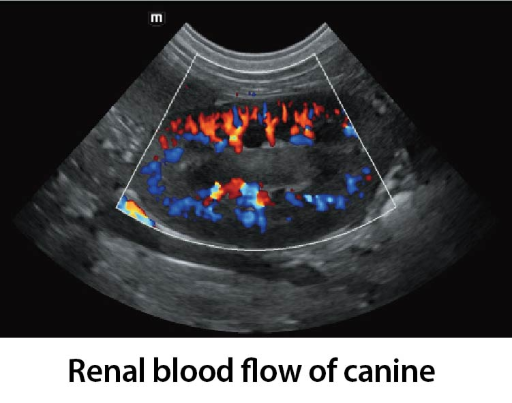

Клинични снимки

Clinical Images